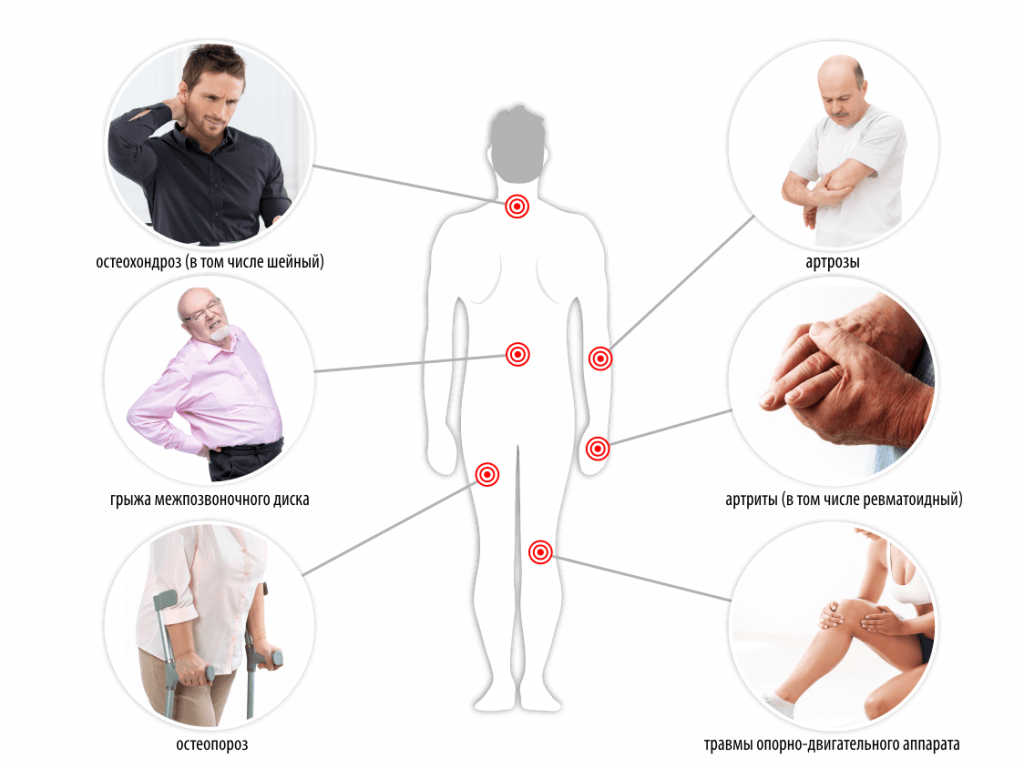

Эффективно устраняет воспаление и боль, снимает спазм и отёк, нормализует кровообращение и обмен веществ, останавливает развитие болезни, способствует восстановлению, улучшает двигательные функции, повышает жизненную активность.Показания к применению Алмаг+:

Артриты, артрозы, остеохондропатии, пяточная шпораДорсопатия (остеохондроз позвоночника, грыжа межпозвоночного диска, сколиоз)

Остеопороз

Поражения отдельных нервных корешков и сплетений верхних и нижних конечностей, в том числе после травм, перенесенного инсульта

Травмы (переломы)